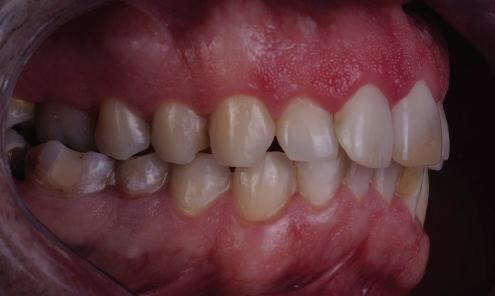

7Dental Tribune Bulgarian Edition / октомври 2022 г. Преди лечението Фиг. 1 Фиг. 4 Фиг. 7 Фиг. 10 Фиг. 13 Фиг. 16 Фиг. 17 Фиг. 18 Фиг. 19 Фиг. 20 Фиг. 11 Фиг. 14 Фиг. 12 Фиг. 15 Фиг. 8 Фиг. 9 Фиг. 5 Фиг. 6 Фиг. 2 Фиг. 3

8 Dental Tribune Bulgarian Edition / октомври 2022 г. По време на лечението Фиг. 21 Фиг. 25 Фиг. 30 Фиг. 31 Фиг. 34 Фиг. 38 Фиг. 40 Фиг. 44 Фиг. 48 Фиг. 50 Фиг. 49 Фиг. 46 Фиг. 39 Фиг. 41 Фиг. 45 Фиг. 47 Фиг. 42 Фиг. 43 Фиг. 35 Фиг. 36 Фиг. 37 Фиг. 32 Фиг. 33 Фиг. 26 Фиг. 28 Фиг. 29 Фиг. 27 Фиг. 22 Фиг. 23 Фиг. 24

9Dental Tribune Bulgarian Edition / октомври 2022 г. След лечението За авторите: Д-р Манол Ивчев е създател на COLDY DENT Functional Atelier, завършва дентална медицина във ФДМ, София. Шест години е стажант в ортодонтска практика. Интересите му са изцяло насочени към функционалната дентална медицина. Посещава курсовете на Доусън и Льо Гал. Преминава редица обучения, акредитирани от Института на Славичек във Виена – VieSID. Впоследствие става най-младият инструктор във VieSID. Придобива права да преподава философията на проф. Рудолф Славичек в България. В практиката си се придържа към протоколите на Славичек за функционално лече ние и диагностика, тъй като те са насочени към комплексно лечение. Завършва всички нива за морфология на зъбите и моделаж при Janos Mako. Повишава знанията си по функционална ортодонтия чрез индивидуален курс в Румъния. Д-р Ивчев е и сертифициран зъболекар по лингвална ортодонтия от Катедрата по ортодонтия от Университета по стоматология в Тегу, Южна Корея. Сертифициран е и за лечение на ортодонтски аномалии чрез миофункционални апарати, а също и за ортодонтия, подпомагана от миниимпланти, отново от Университета по стоматология в Южна Корея. Завършва индивидуално обучение по функционална ортодонтия в Университета по дентална медицина в Богота, Колумбия, както и индивидуално обучение по функционална ортодонтия и физиотерапия по про токола на Mariano Rocabado. Има завършено индивидуално обучение по функционална зъботехника и функционален Wax-Up клас I,II и III. Завършва курс за Digital Smile Design и Skin Concept в Люксембург при Christian Coachman, Florin Cofar, Paulo Kano, Josef Kunkela, Livio Yoshinagа. Зт. Leandro Gambogi, Бразилия, завършва зъботехника през 1999 г. Експерт и пионер в дигиталната диагностика. Лектор и инструктор на курсове в областта на дигиталното протезиране. Понастоящем е главен изпълнителен директор и зъботехник в DENTALE DIGITAL LAB. В периода януари 2005 г. – декември 2006 г. завършва бизнес управление и администрация в Methodist University Center Izabela Hendrix. Съавтор на книгата Odontologia Digital: Desafiando os Limites, глава 5: „Дигитално включване във времето. Технология CAD/CAM“. Преминал множество обучения при световноизвестни кли ницисти. Фиг. 51 Фиг. 54 Фиг. 57 Фиг. 58 Фиг. 63 Фиг. 64 Фиг. 65 Фиг. 59 Фиг. 61 Фиг. 62 Фиг. 60 Фиг. 55 Фиг. 56 Фиг. 52 Фиг. 53 Фиг. 66